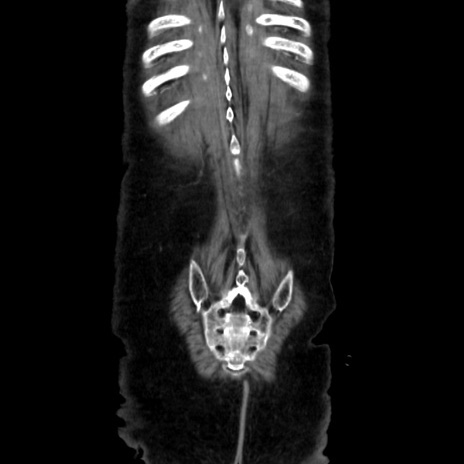

【症例】90歳代女性

【主訴】腹痛・嘔吐

【現病歴】 食欲低下、嘔吐があり昨日他院受診。肺炎と診断され入院となる。入院後より腹部全体に圧痛あり。胃管留置され経過みていたが、症状持続するため、

当院転院となる。

【既往歴】胸椎圧迫骨折、胆石症

【身体所見】腹部:中央に激痛あり、圧痛あり、反跳痛不明

【データ】WBC 17100、CRP 18.82

矢状断像